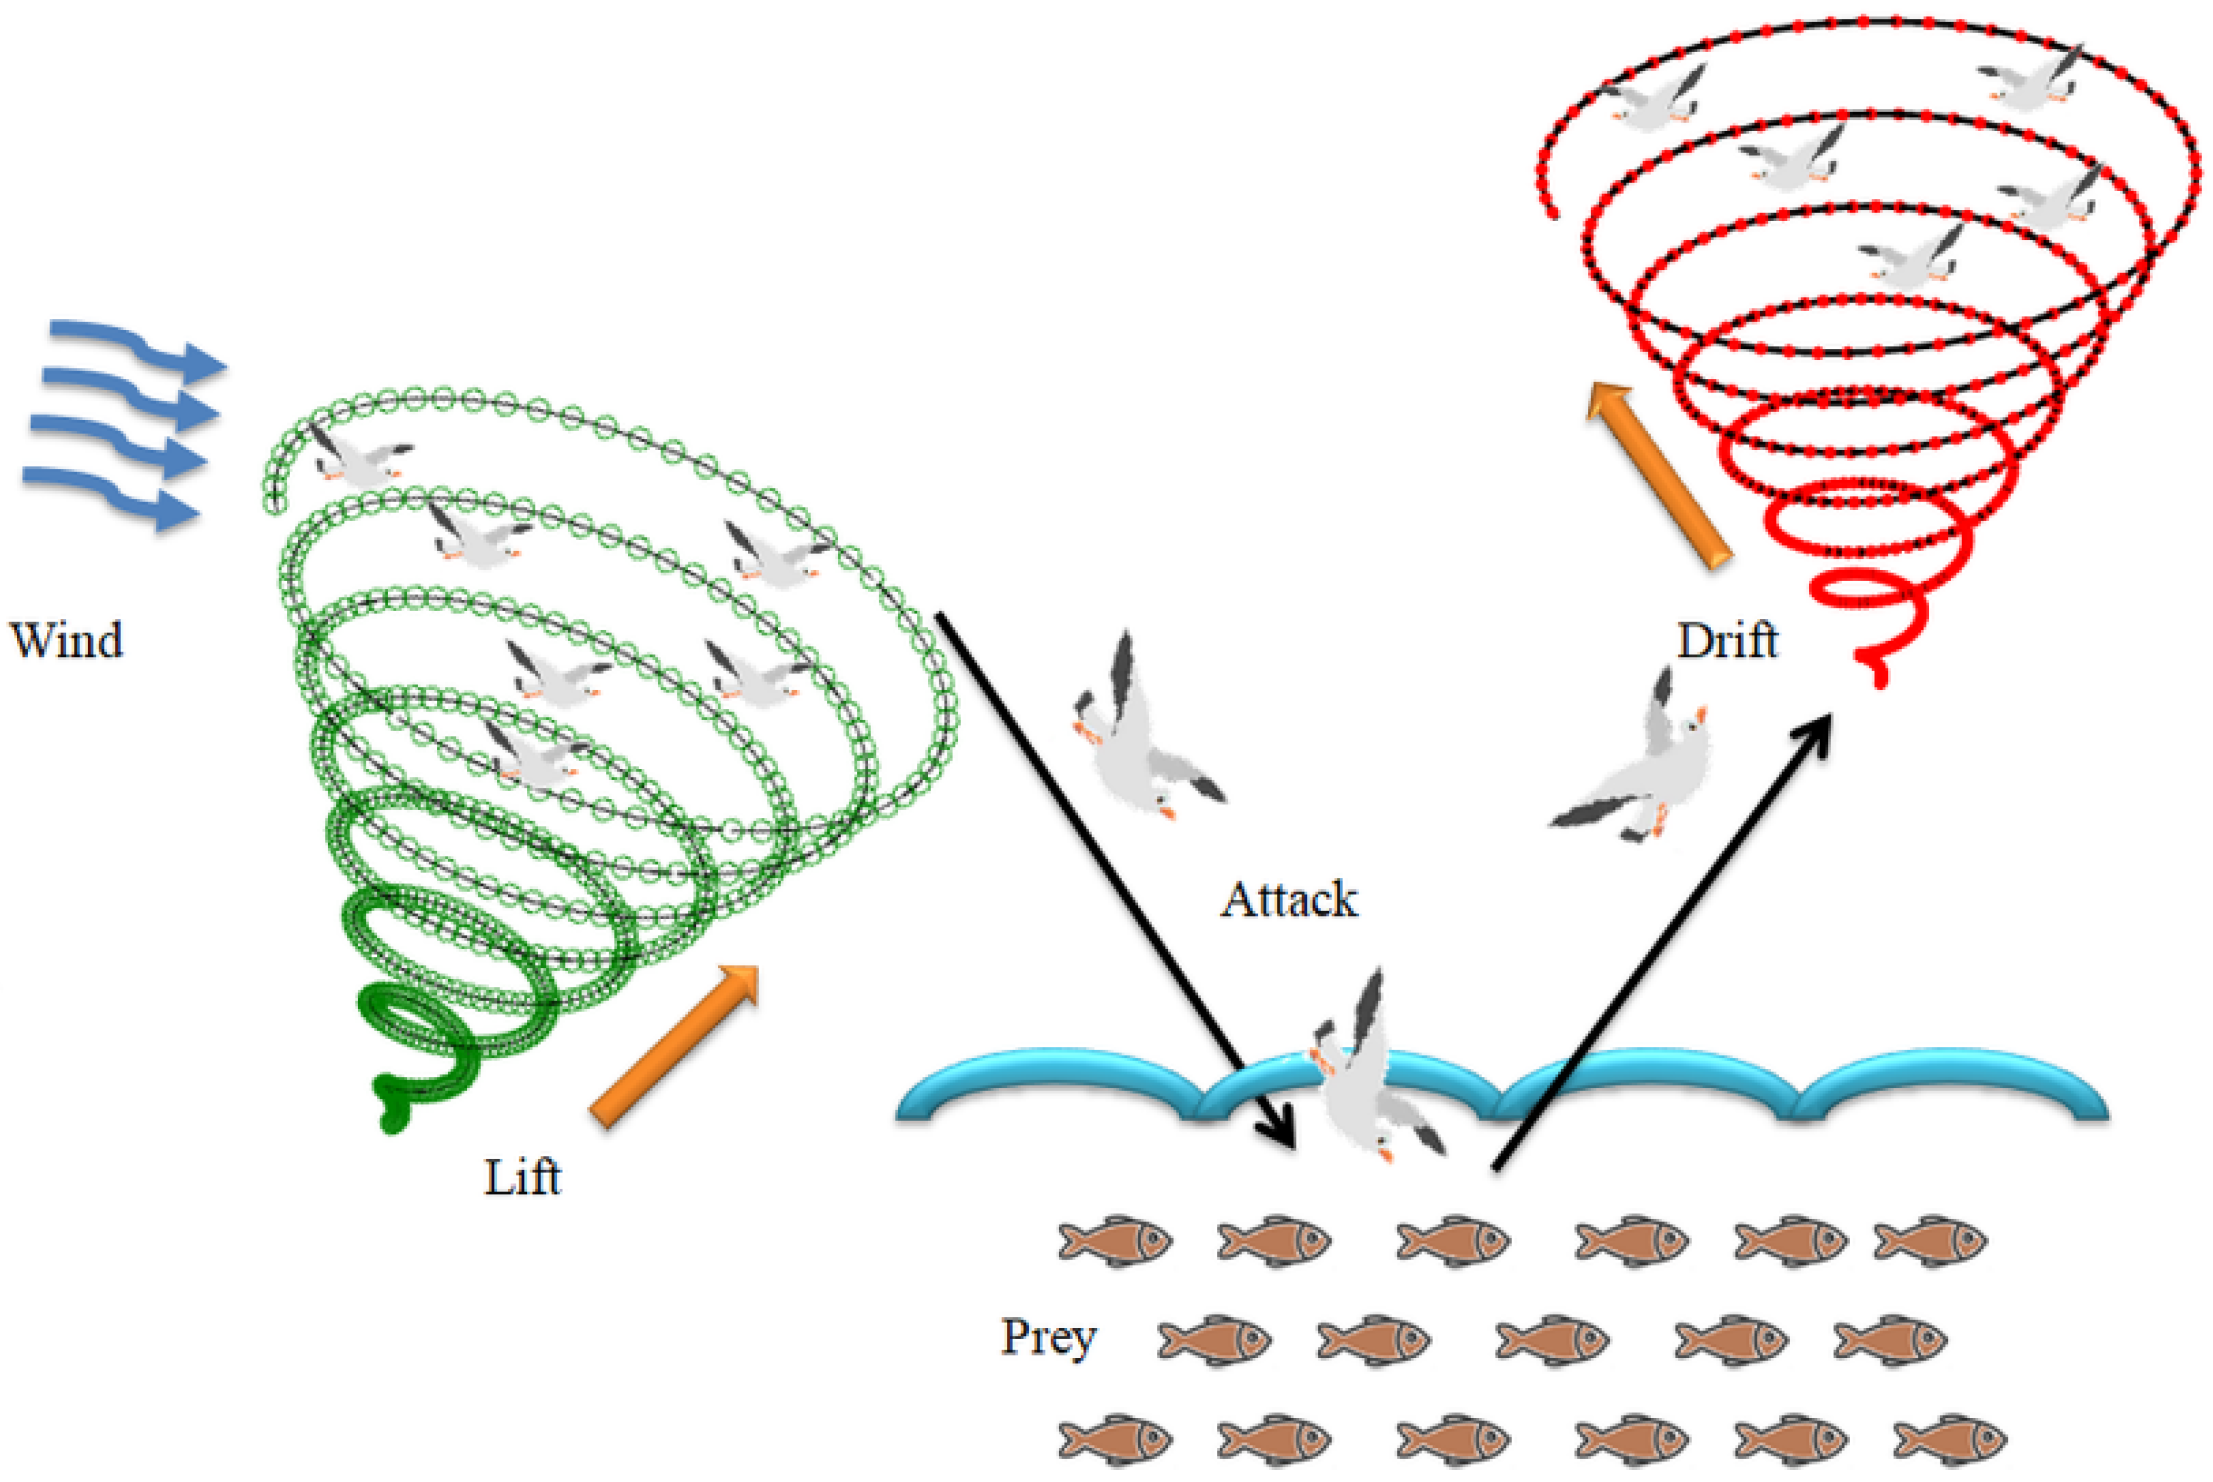

3.4. Seagull-Algorithm Based Feature Optimization

3.4.1. Migration as a Group to Find Fish Swarm (Exploration)

3.4.2. Attacking the Fish (Exploitation)